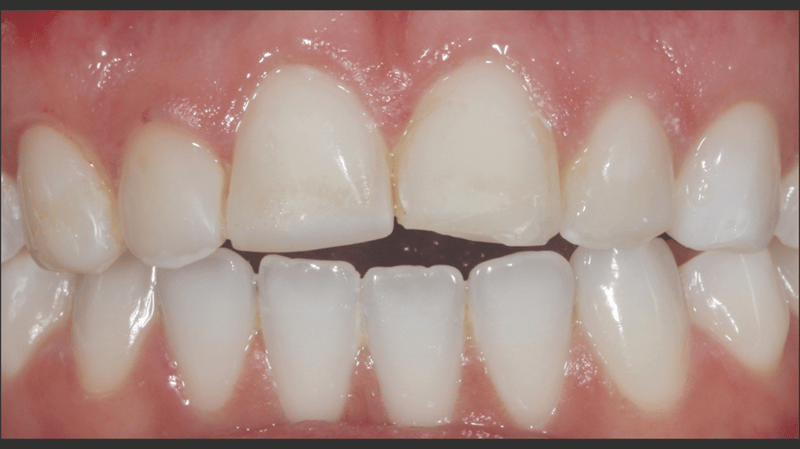

A young woman in her 20s, burdened by the discoloration of her upper anterior teeth from past trauma, came to Dr. Jaleena Fischer-Jessop, DDS, MBA, searching for a solution that would restore her smile. The patient was treated with a conservative and cost-effective solution: no-prep direct-bonded composite veneers. Dr. Fischer-Jessop chose this method to mask the discoloration and match the patient’s upper teeth with the lower anteriors—avoiding the need for more invasive procedures like implants or costly lab processed veneers. The shades B1D and Enamel White (EW) were selected to lighten the teeth and Transcend™ composite’s Universal Body (UB) shade was used to ensure the margin blended naturally into the cervical areas.

- Esthetic Concerns and Financial Considerations: The patient expressed concerns about the appearance of her teeth and was financially constrained. Given the circumstances, no-prep direct-bonded composite veneers were chosen as the solution.

The procedure successfully addressed the patient’s esthetic concerns by masking the discoloration of her upper anterior teeth and achieving a natural, balanced look with her lower anteriors. The use of no-prep direct-bonded composite veneers provided a conservative, highly effective solution that respected both the patient’s financial constraints and desire for minimal invasiveness.